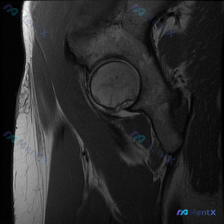

看到一份髋关节冠状位T1加权MRI的病例资料,在股骨头外侧下方至股骨颈内侧区域发现一个局灶性的异常信号灶。病灶呈类圆形,边缘相对清晰,信号强度与周围肌肉相近(等信号)。 有人认为这个病灶可能是盂唇病变相关(盂唇旁囊肿或盂唇内囊肿),但也有观点提出可能是其他类型的软组织结节。大家可以结合以下信息讨论:...

看到一份髋关节MRI影像分析报告,患者的核心关注点是盂唇病变,但当前仅提供了单张T1加权冠状位MRI影像。报告分析指出: - T1序列对盂唇撕裂(尤其是无移位小撕裂)或退变显示能力有限 - 影像未见明显股骨头坏死、骨折等异常 - 需结合T2压脂序列、MR关节造影(MRA)等全面评估 - 还提到了关节...

整理了一份髋部MRI病例讨论材料,患者可能有髋关节疼痛或相关症状,临床怀疑盂唇病变。先放这张冠状位T2加权影像,大家看看能不能诊断盂唇病变? 影像特点: - 股骨头形态圆润,信号均匀 - 髋关节间隙正常,软骨厚度均匀 - 髋臼盂唇呈低信号三角形,形态规整 - 周围软组织无明显异常 欢迎大家讨论自己的...